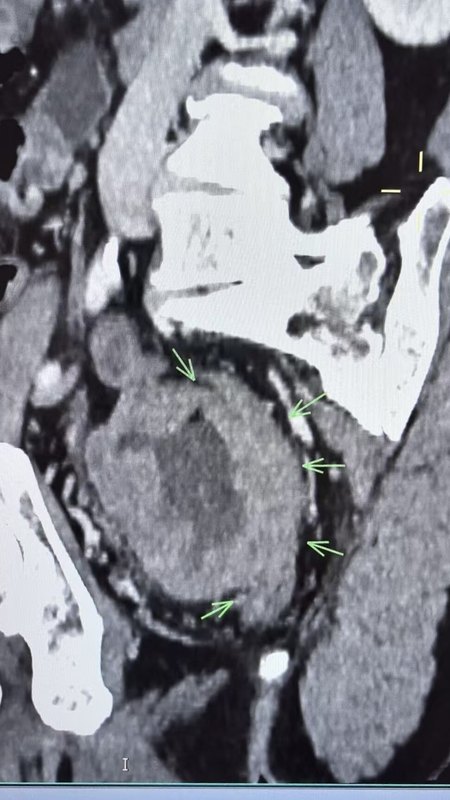

周末在家鄉(xiāng)縣醫(yī)院與當(dāng)?shù)蒯t(yī)生協(xié)作完成一例考慮胃間質(zhì)瘤內(nèi)鏡下EFTR術(shù)(全層切除術(shù))?;颊呶哥R查出2-3cm黏膜下隆起,質(zhì)地較韌,胃內(nèi)此種病變絕大多數(shù)考慮間質(zhì)瘤。因當(dāng)?shù)乜h醫(yī)院超聲內(nèi)鏡購(gòu)買中,還未到位?;颊哂值膺^(guò)敏,因此術(shù)前只能行上腹部CT平掃,充分喝水撐開(kāi)胃腔后,瘤子輪廓較清晰。溝通交流后,家屬充分信任,考慮內(nèi)鏡下微創(chuàng)切除。手術(shù)非常順利,瘤子完整切除,避免了外科腹腔鏡/開(kāi)腹手術(shù)。術(shù)后病灶性質(zhì)明確及是否需要進(jìn)一步靶向藥口服等有待進(jìn)一步病理評(píng)估。結(jié)合病例診療談?wù)剮c(diǎn)感悟:1.充分的術(shù)前評(píng)估很重要,有時(shí)候不可能裝備精良,那也得用好手頭已有的武器,此例患者沒(méi)有做超聲內(nèi)鏡條件,術(shù)前CT評(píng)估做得很漂亮,患者自身準(zhǔn)備的好,水喝的很足,病灶顯示也很清楚。2.多與相關(guān)科室進(jìn)行討論,術(shù)前與兄弟科室普外科交流討論,明確手術(shù)適應(yīng)癥、禁忌癥。做好多種方案,有備無(wú)患。3.與患方多溝通交流,解答對(duì)方困惑,建立良好醫(yī)患信任?;挤椒菍I(yè)人士,難免有困惑及焦慮。淺顯易懂將治療相關(guān)原理與可能發(fā)生情況及應(yīng)對(duì)策略告知他們后,不但有助于他們解除困惑及焦慮,也有助于建立和諧醫(yī)患關(guān)系。4.引用我科熊光蘇主任科普相關(guān)文@消化內(nèi)鏡熊光蘇醫(yī)生。消化道疾病提倡早診治療,以胃腸道間質(zhì)瘤為例。絕大部分小瘤子(小于1cm)可以選擇定期內(nèi)鏡隨訪,但是越大的瘤子,惡變風(fēng)險(xiǎn)越大(量變引起質(zhì)變),較大的瘤子還是建議切除,具體是內(nèi)鏡還是外科還需具體評(píng)估。5.對(duì)于一些交界性大小病變(例如1cm左右的),切還是不切的糾結(jié)問(wèn)題。我個(gè)人建議是:綜合年齡及患者個(gè)人心態(tài),如果能夠接受定期復(fù)查不想切,可以選擇隨訪。如果心態(tài)上就有定時(shí)炸彈????思想,那還是早點(diǎn)前往權(quán)威醫(yī)院尋求經(jīng)驗(yàn)豐富醫(yī)生行切除治療,一勞永逸。